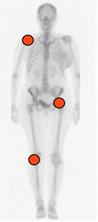

Es mas frecuente en la rodilla, seguido por la cadera y el hombro. (Fig 69).

Fig 69. Distribución de la condromatosis sinovial.

Alteración monoarticular, de articulaciones grandes.